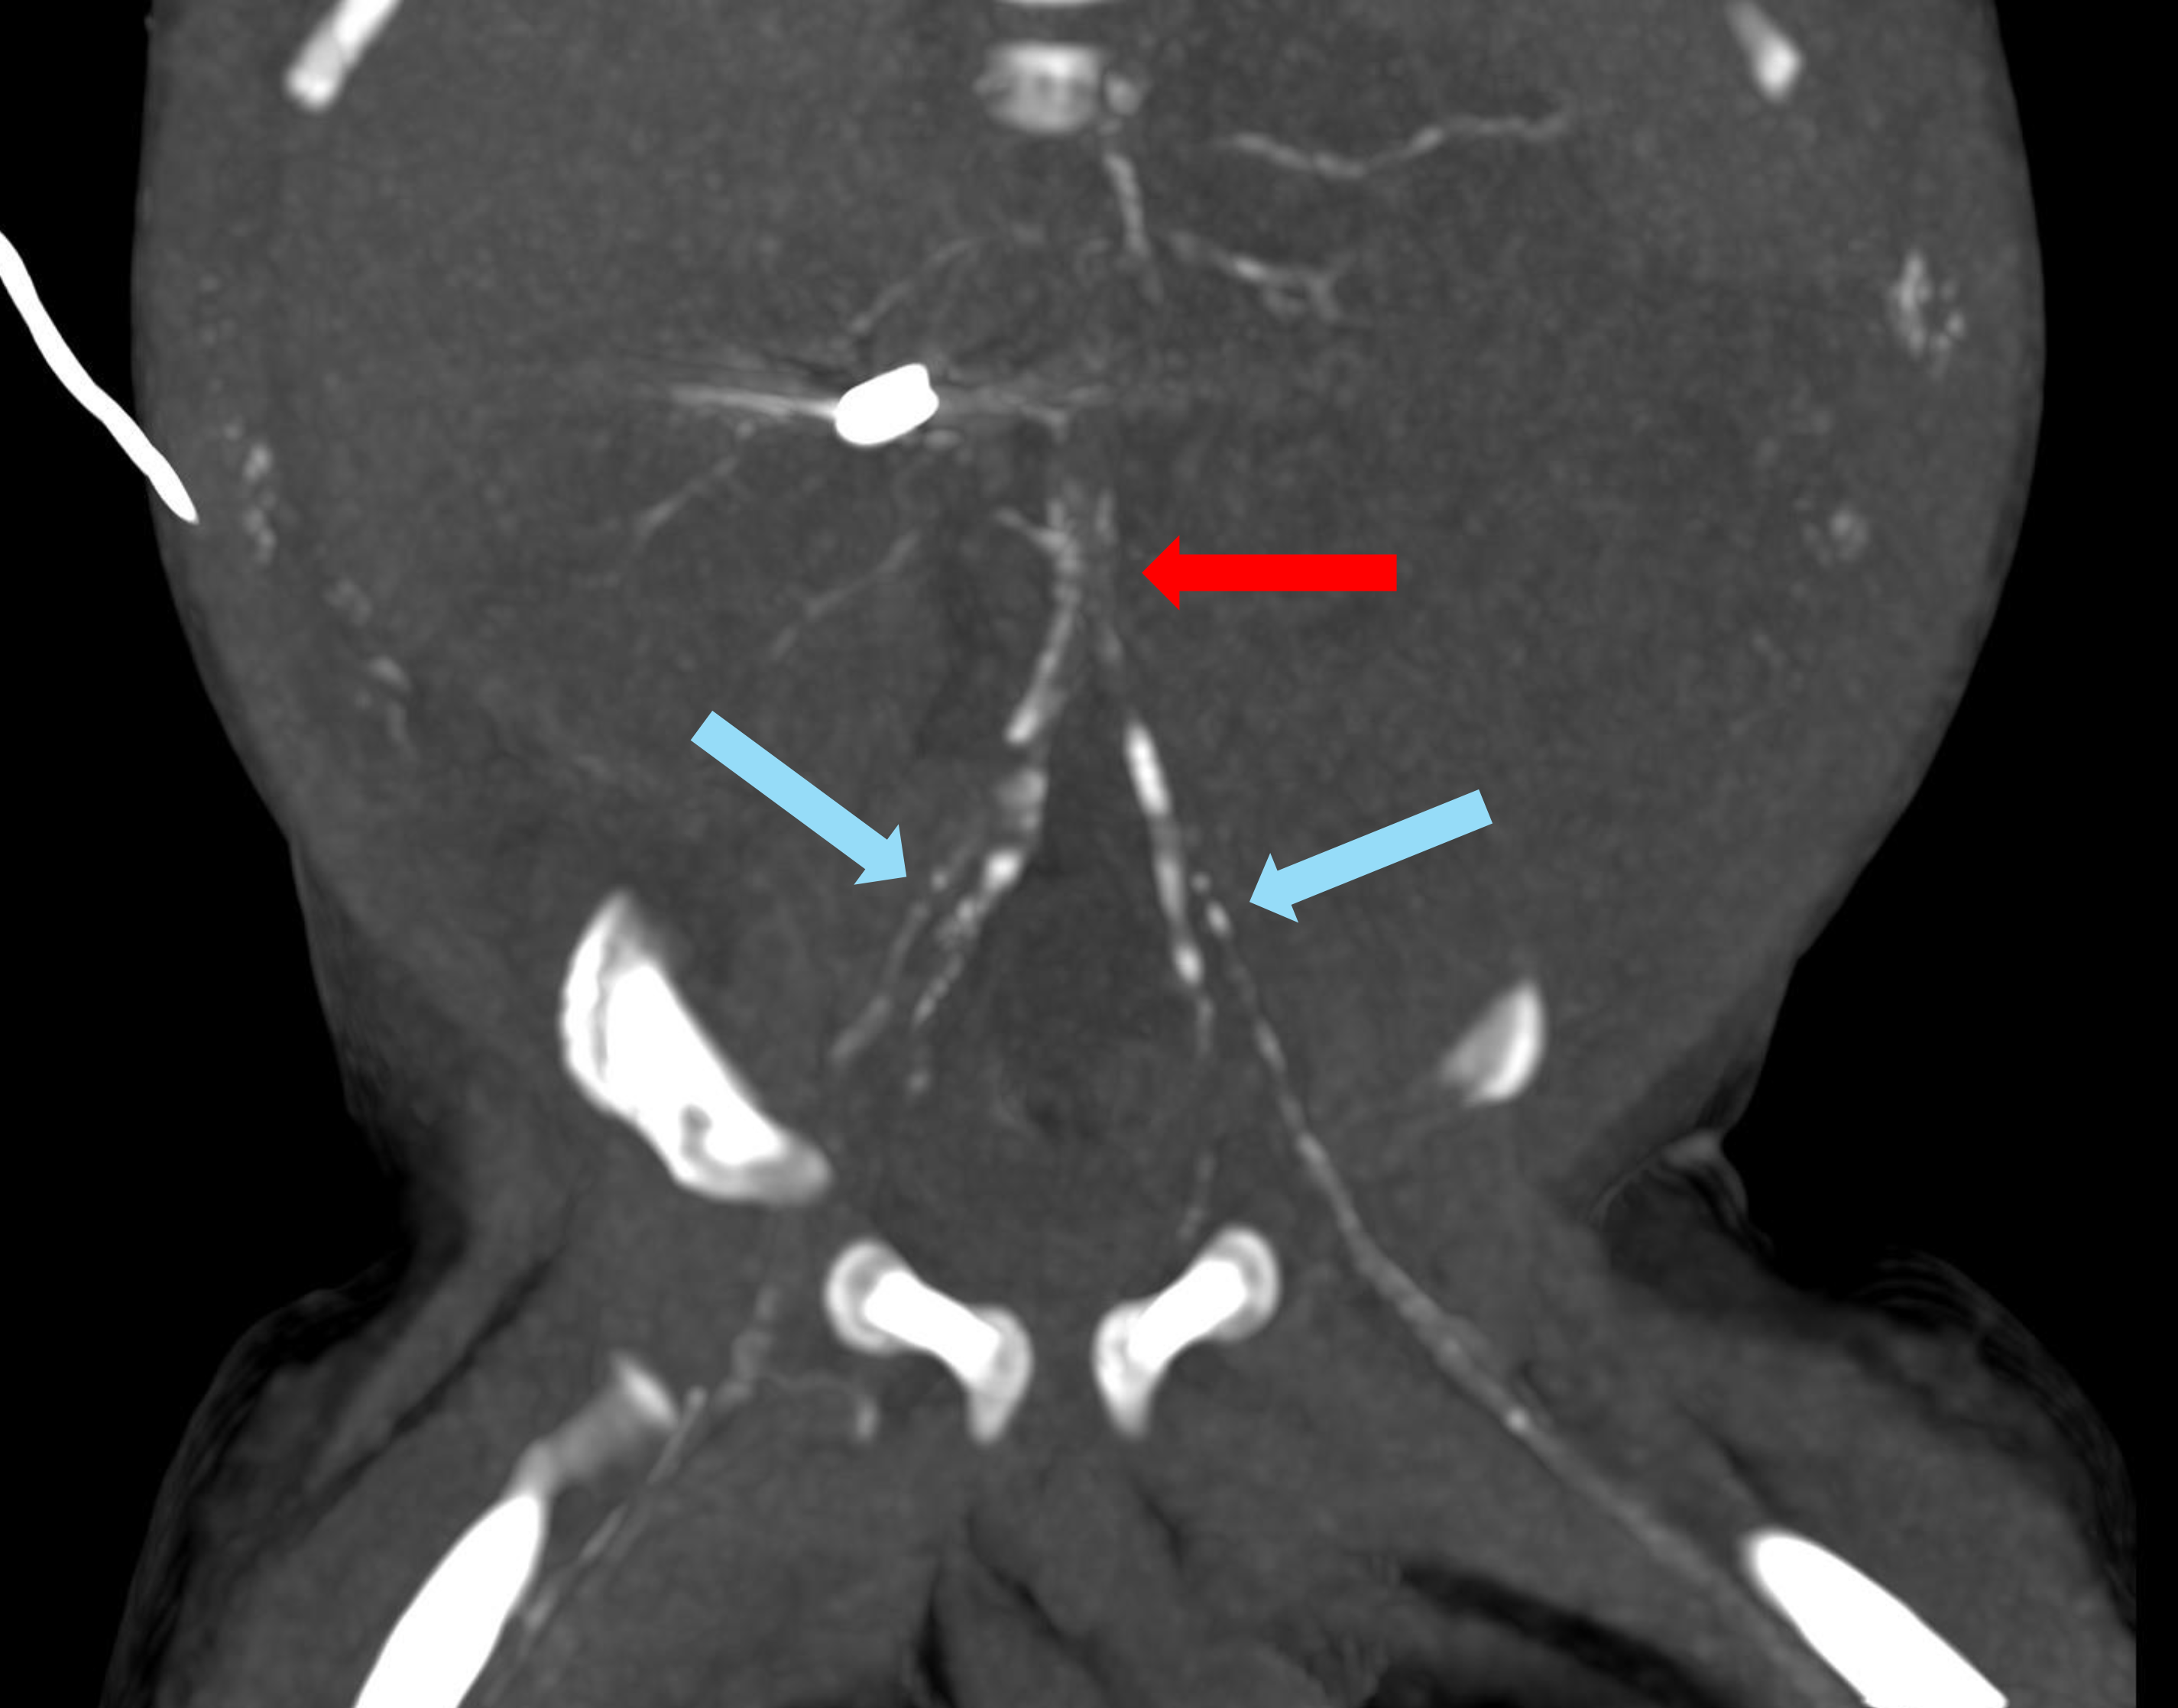

The infant had generalized arterial calcification of infancy (GACI), which can usually be confirmed with genetic testing. Video 1 is a four-chamber view from a fetal echocardiogram showing right atrial dilation, mildly depressed right ventricular systolic function, and a small circumferential pericardial effusion. Video 2 is a sweep from the fetal echocardiogram through the main and branch pulmonary arteries showing thickened, echobright vessel walls. Videos 3 and 4 are transthoracic echocardiogram clips showing echobright walls of the ascending aorta and right pulmonary artery (Figure 1). The echobright appearance of the aorta and pulmonary arteries is strongly suggestive of arterial calcification and typical of GACI. Among the answer choices, genetic testing is most likely to confirm the diagnosis. Thus, answer choice A is the correct choice.

Figure 1: Transthoracic Echocardiogram Clips Showing Echobright Walls of the AAo and RPA

(Panel A) Fetal echocardiogram short-axis view of the MPA (blue arrow) and branch PAs showing echobright vessel walls consistent with arterial calcification. (Panel B) Transthoracic echocardiogram subcostal transverse view showing the AAo (red arrow) and proximal RPA (blue arrow) with echobright walls.

AAo = ascending aorta; LV = left ventricle; MPA = main pulmonary artery; PAs = pulmonary arteries; RPA = right pulmonary artery; RV = right ventricle.